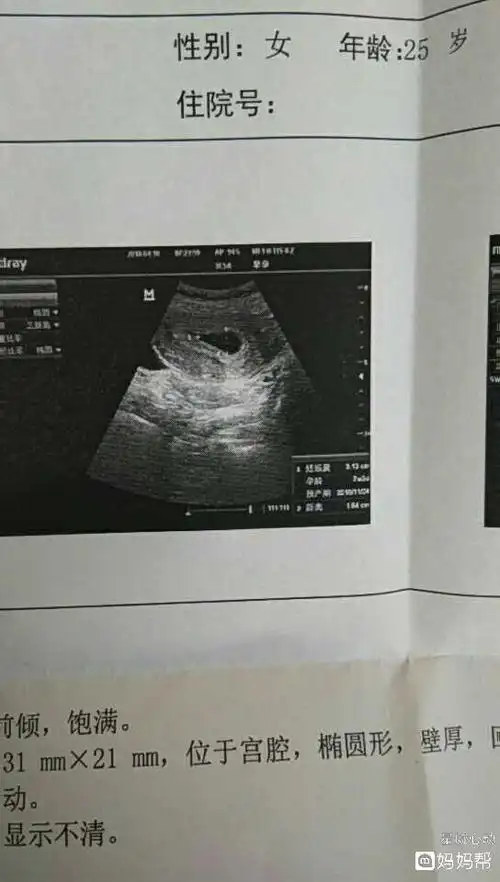

看到孕囊啦

末次月经六号,月经周期30天到32天,这到底是个什么鬼,为啥孕囊只有3